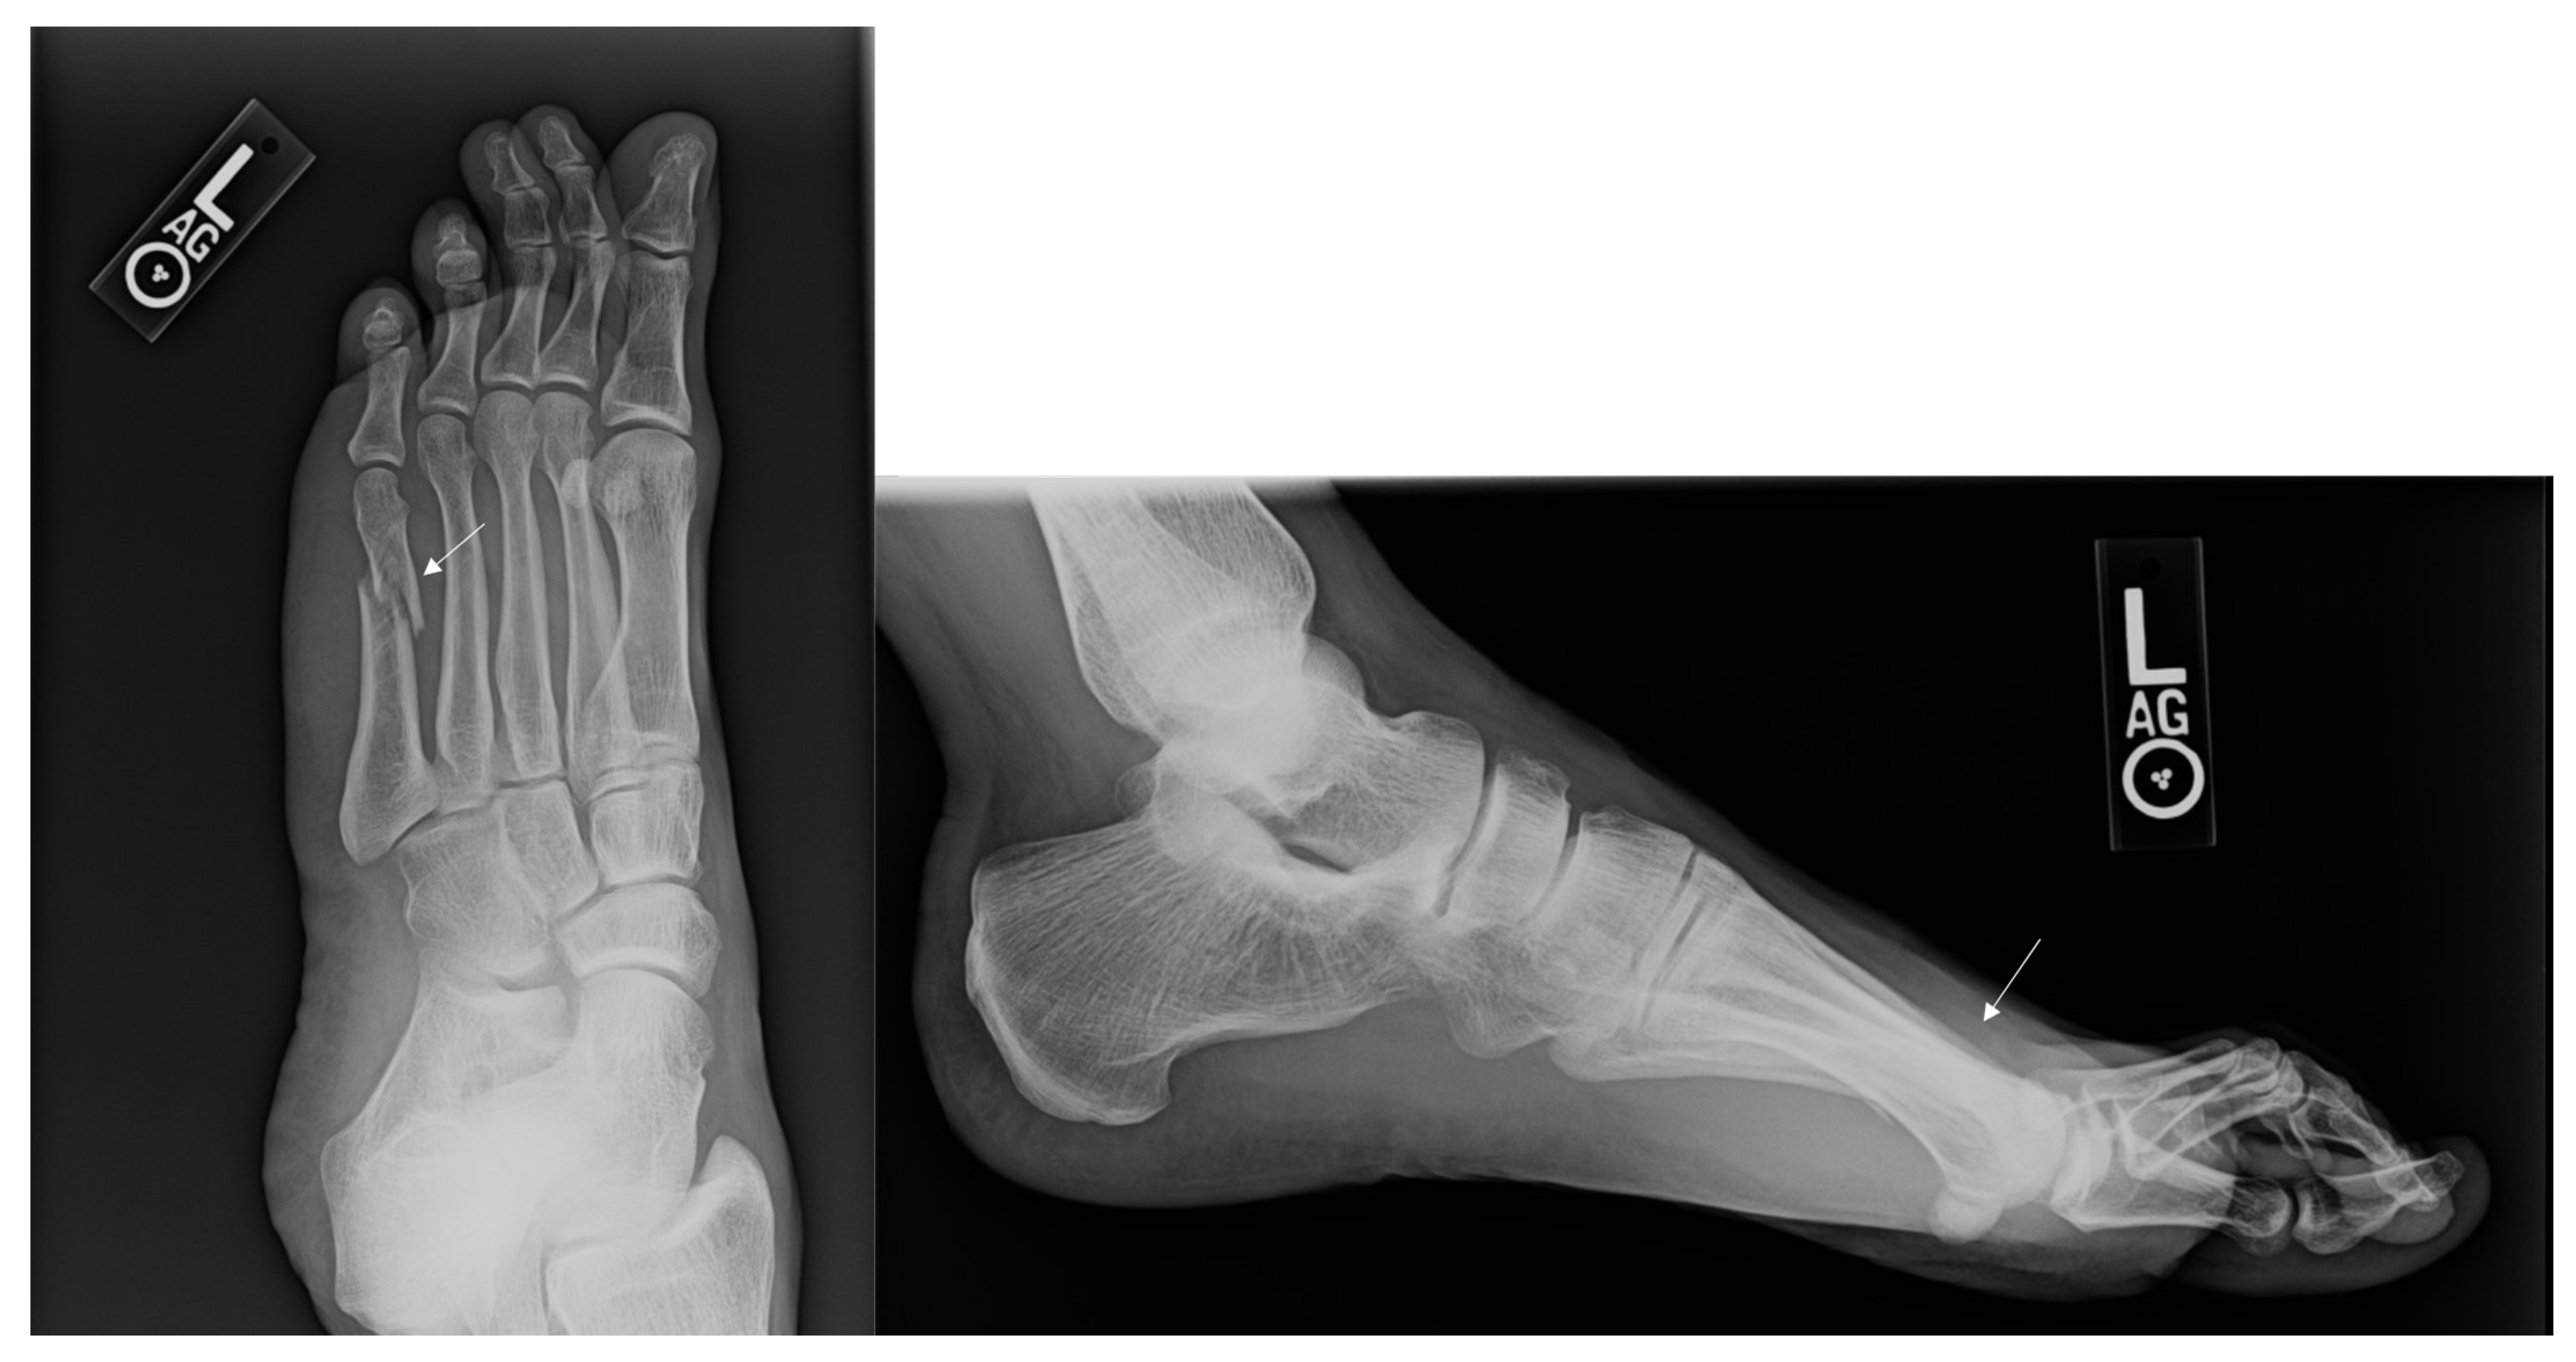

Figure 3.

Radiographs of a Metatarsal Fracture Displaced 3–4 mm. Displayed above are radiographs of a fifth metatarsal shaft fracture that is displaced between 3–4 mm. The arrows above identify the fifth metatarsal fracture.

Figure 4.

Radiographs of a Metatarsal Fracture Displaced Greater than 4 mm. Displayed above are radiographs of a fifth metatarsal shaft fracture displaced greater than 4 mm. The arrows above identify the fifth metatarsal fracture.

If only those patients with greater than 4 mm of displacement were considered operative candidates based upon guidelines, 5 fractures would have met criteria for surgery. Four of those 5 cases were actually treated with an operation at the time of injury. The one case that was initially treated non-operatively later developed a non-union and underwent a non-union repair. It should be noted that the fracture which developed a non-union in this grouping was secondary to gunshot injury to the foot (Figure 1 and Figure 2). The patient who developed a non-union was unable to return to run at final follow-up. Of the 4 patients initially treated operatively, 1 was unable to return to running secondary to pain at the fracture site.